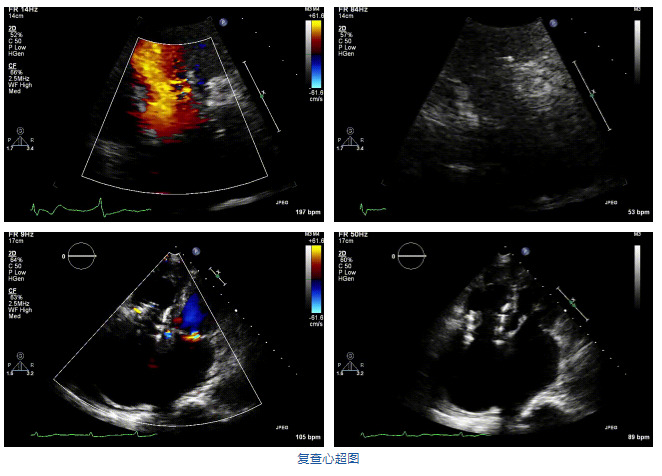

2021年12月7日,復旦大學附屬中山醫(yī)院葛均波院士團隊完成的首批兩例LuX-Valve Plus經(jīng)血管三尖瓣置換患者順利出院,從患者入院至出院僅歷時一周時間,出院時患者狀態(tài)恢復良好,復查心超三尖瓣無反流。

結合術前CT評估結果,葛均波院士團隊最終決定選用LuX-Valve Plus 50mm和55mm兩種型號的瓣膜,并于2021年11月30日順利完成LuX-Valve Plus經(jīng)血管三尖瓣置換術,手術室即刻拔除氣管插管,術后第二天轉(zhuǎn)出心內(nèi)科監(jiān)護室,下床活動。術后患者三尖瓣反流癥狀得到顯著改善,復查心超結果顯示人工三尖瓣瓣膜支架固定穩(wěn)定,瓣葉關閉形態(tài)未見異常,未見明顯反流。

在本次救治性臨床研究中,治療的兩例患者病因不同,解剖結構復雜,均為極重度三尖瓣反流,手術最終都順利植入了LuX-Valve Plus三尖瓣人工瓣膜。術后超聲顯示瓣膜支架固定穩(wěn)定,反流癥狀顯著改善,取得了良好臨床治療效果。